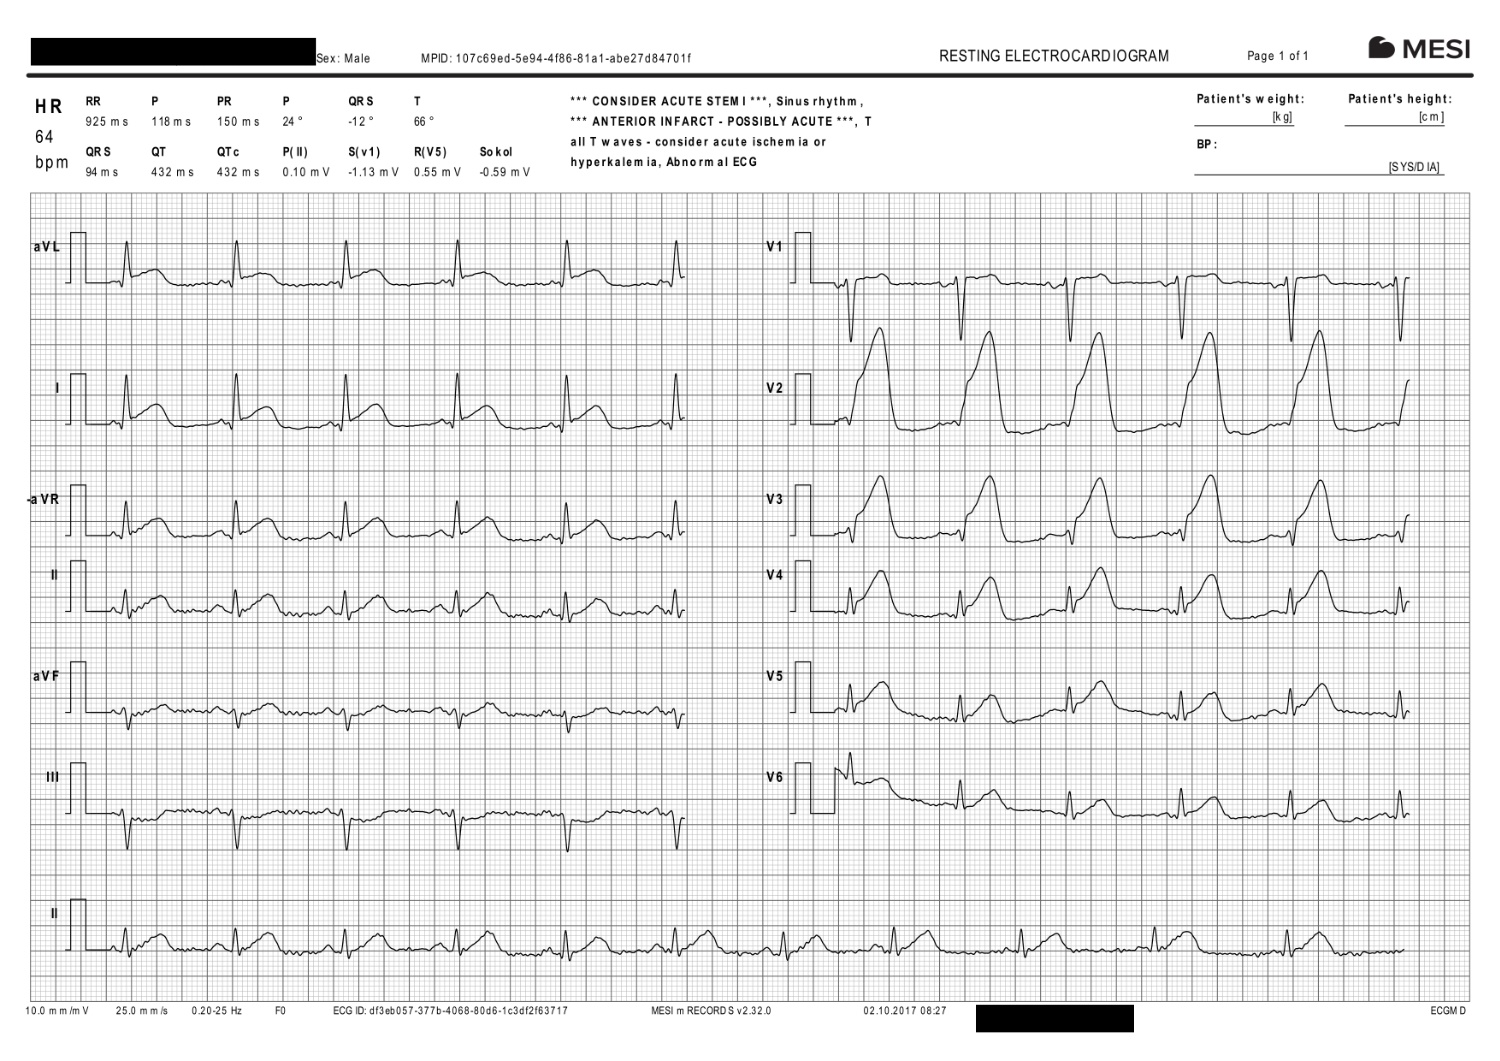

Dr. Pecev stellte fest, dass der Patient sichtbare, typische Anzeichen eines Myokardinfarkts aufwies, wie Schmerzen, Blässe und Schweißausbrüche. Die Vitalfunktionen lagen im normalen Bereich, aber das EKG bestätigte schließlich den Ernst der Lage. Dr. Pecev sagt:

„Das MESI mTABLET ECG hat uns sehr geholfen, denn wir konnten den Patienten kontinuierlich überwachen und ständig EKGs aufzeichnen. Nachdem der Patient einige Minuten lang an das EKG angeschlossen war, traten die ersten Anzeichen eines Herzinfarkts auf.“

Nach etwa 10-15 Minuten zeigte das MESI mTABLET einen deutlichen Herzinfarkt (STEMI) – Erhöhungen in den vorderen und seitlichen Wandableitungen.